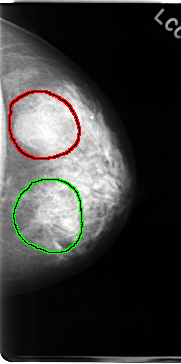

C_0062_1.LEFT_MLO

LEFT_MLO LINES 4640 PIXELS_PER_LINE 2432 BITS_PER_PIXEL 12 RESOLUTION 50 OVERLAY

FILE: C_0062_1.LEFT_MLO.OVERLAY

TOTAL_ABNORMALITIES 2

ABNORMALITY 1

LESION_TYPE MASS SHAPE IRREGULAR MARGINS ILL_DEFINED

ASSESSMENT 4

SUBTLETY 2

PATHOLOGY MALIGNANT

ABNORMALITY 2

LESION_TYPE MASS SHAPE LOBULATED MARGINS CIRCUMSCRIBED

ASSESSMENT 3

SUBTLETY 5

PATHOLOGY BENIGN